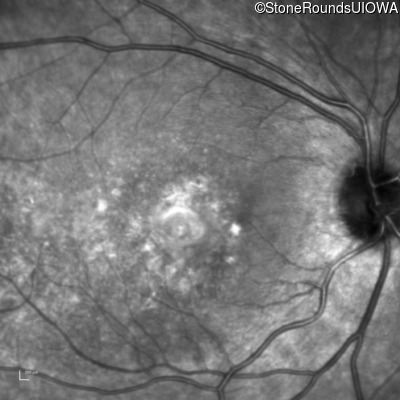

Best Disease (IIB)

Age at visit: 14 years

This 15 year old girl came to medical attention during a routine athletic vision screening when the acuity in her right eye was observed to be abnormal.

Diagnosis & molecular findings

Disease Gene Allele 1 variant(s) Allele 2 variant(s) Inheritance mode

Best Disease BEST1 Asp228Glu GAC>GAG Asn259 ins2aacAA AR